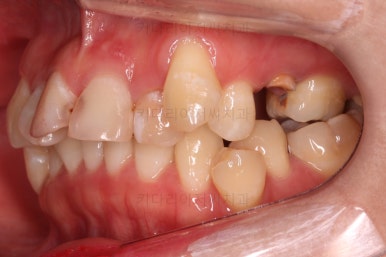

초진 시 입안의 모습입니다.

이미 썩어서 부러진 치아도 몇 개 보이고요.

많이 삐뚤어진 치아쪽은 양치가 힘들어 이미 많이 썩어 있는 상태에 덧니쪽은 잇몸도 많이 내려간 상태였습니다.

말그대로 교정치료 뿐만 아니라 전반적인 치료가 필요한 상황이었습니다.